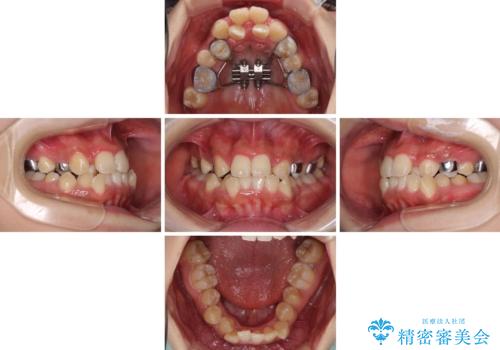

前後に重なった前歯 ワイヤー装置と急速拡大装置を併用したインビザライン矯正

- 前歯の著しい叢生とクロスバイトを気にして来院された患者様です。

叢生が強いため、一見すると抜歯矯正と判断したくなりますが、下顎臼歯が舌側に倒れていることから、上顎骨を側方拡大し、非抜歯矯正の可能性を検討することとしました。

非抜歯矯正が可能となった場合には、インビザラインにて矯正治療を行うこととしました。

急速拡大装置による上顎骨の側方拡大が思った以上にうまくいき、非抜歯での矯正が可能となりました。

内側に倒れていた下顎の臼歯は起き上がり、清掃性も大幅に改善されました。